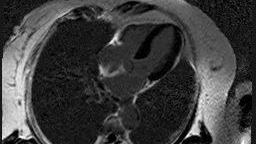

您是否曾因不明原因的心悸、胸闷、气短而担忧?面对复杂的心肌病变、心肌梗死后的评估,是否渴望一份更精准、更直观的“心脏报告”?  现在,北京大望路急诊抢救医院(原北京朝阳急诊抢救中心)为您带来了心脏疾病诊断的“金标准”之——心脏核磁增强(CMR)检查,并已成功完成30余例临床应用,技术成熟,效果显著!                                                                                               技术升级,时间更短,耐受更好  传统心脏核磁检查时间长是困扰患者的一大难题。心脏核磁增强技术的开展极大地解决了扫描时间长、患者不好耐受的问题。  我院医护人员通过对打药前后心脏电影序列的对比研究,发现打药后扫描心脏电影序列能够取得与打药前相同的效果。  借助这一发现,科室对检查流程进行了优化:由于心肌需要进行延迟强化,在等待的这段时间里扫描电影序列,不仅充分利用了等待时间,还显著缩短了患者的整体检查时间。原本需要40分钟的检查,现在缩短到了30分钟左右,大幅提升了患者的检查体验。     适用于哪些情况?  心脏核磁增强技术以其无创、无辐射、软组织分辨率极高的优势,能提供心脏全方位的精细影像:  1.精准评估心脏结构与功能:清晰显示心脏大小、室壁厚度、心室腔容积,精确计算心脏射血分数(EF值)等关键功能指标。  2.明辨心肌病变性质: 是诊断心肌炎、扩张型心肌病、肥厚型心肌病?等非缺血性心肌病的利器,帮助区分病因,指导治疗。  3.评估心肌活力与梗死范围: 对于心肌梗死患者,能清晰地显示坏死心肌(延迟强化区域)、冬眠心肌及健康心肌的范围和程度,是判断预后、制定治疗方案(如血运重建必要性)的关键依据。  4.发现占位与血栓:有效识别心脏肿瘤、心腔内血栓等病变。     检查前温馨小贴士  为了确保您获得最清晰、最准确的检查结果,请您在检查前注意:  心率要求:检查时心率最好控制在75次/分钟以下。  心律要求:心律需相对整齐。如有严重心律失常,可能会影响图像质量和检查效果,请提前与医生沟通。     守护心脏健康,我们更专业!  自去年开展以来,我院心脏核磁增强项目已累计为30余例患者提供了高质量的检查服务,覆盖了多种常见及复杂心脏疾病,积累了丰富的本地化操作和诊断经验,为临床医生提供了强有力的影像学支持,显著提升了对心肌疾病的精准评估能力。  北京大望路急诊抢救医学影像科,依托先进的设备、优化的流程和专业的团队,致力于为您提供更快捷、更舒适、更精准的心脏核磁增强检查服务。让高清影像照亮“心”世界,为您的健康心脏保驾护航!     医学影像科简介     北京大望路急诊抢救医院(原北京朝阳急诊抢救中心)医学影像科分设于南、北两个院区,集X线、CT、骨密度仪、磁共振成像为一体的综合性科 室,拥有全自动固定DR三台,移动DR三台,64排CT一台,16排CT两台,40排CT一台。1.5T、 3.0T核磁各一台。骨密度仪一台。可以满足各种临床诊治需求,开展神经系统、头颈部、呼吸系统、循环系统、消化系统、泌尿生殖系统、骨骼肌肉系统等全身各系统综合性影像检查和诊断。科室人员经验丰富,梯队合理,现有专业技术人员29人,其中高级职称3人(主任医师兼主管技师一人)。 学科带头人  白志勇,放射科主任,主任医师兼主管技师,从事影像技术及诊断工作27年,熟练掌握常见病、多发病的影像诊断,对疑难病例有自己独特的见解,擅长各部位血管CTA的临床实践、影像后处理及诊断。原三甲医院CT/MRI室副主任。在《中国CT/MRI杂志》《实用放射学杂志》《内蒙古医学杂志》《河北医学杂志》等国家级、省级医学杂志发表论文10余篇。获得赤峰市政府“二等功”,红山区政府“三等功”奖励;内蒙古民族大学赤峰临床医院(赤峰市第二医院)教学能手“三等奖”;红山区卫生系统“先进个人”等奖励。北京医学会放射技术分会第九届CT学组委员、北京神经内科学会神经疾病预防与脑健康专业分会第一届委员。 检查项目  全身各部位CT血管成像(冠状动脉CTA、肺动脉CTA、胸腹主动脉CTA、头颈动脉CTA、下肢动 静脉成像等)、CT各部位平扫及增强扫描、CT支气管树重建、CT立体三维(3D)重建成像技术、CT早 期肺癌筛查技术、CT定位下穿刺活检技术、CT引导下的射频消融;MRI各部位平扫及增强扫描、 MRI功能成像、MRI水成像、MRI弥散成像、MRI扩散张量成像、MRI磁敏感加权成像、MRI波谱成像、 核磁高分辨率血管壁成像,心脏核磁增强成像等。  如有相关检查需求或疑问,欢迎咨询我院医学影像科。咨询电话:010-59298942;1800138****。     心血管内科简介  心血管内科为我院的特色科室之一,科室本着“以患者需求为中心”的原则,倡导人性化服务、个性化服务,让患者安心、舒心、放心。科室开展经皮冠状动脉造影术、冠状动脉内球囊扩张术、冠状动脉内支架植入术、冠状动脉内血栓抽吸术、冠状动脉血管内超声检查、主动脉球囊反搏术;临时起搏器置入、人工永久起搏器植入术,心脏自动转复除颤器植入术(ICD)。床旁心包穿刺术及其他床旁有创操作。经静脉药物溶栓治疗心肌梗死、床旁电除颤转复房颤、室速;具备冠心病中心监护系统。针对心力衰竭及冠心病患者开展特色性的心脏康复治疗,制定个体化药物处方、运动处方及营养处方,进行双心治疗及睡眠管理、戒烟指导及危险因素管理等。   学科带头人  计晓玲,心血管内科主任,主任医师,硕士生导师,心内科常见病、多发病的诊治:如高血压病、高脂血症、冠心病、瓣膜病、心肌病、急性心梗、结构性心脏病、心力衰竭、心律失常等各种心脏重症;擅长心脏电生理:如冠脉内支架植入术、起搏器及ICD植入等。  出诊时间:周二8:00-11:30;周四8:00-11:30、13:30-17:00  出诊地点:北京大望路急诊抢救医院南区   如有相关检查需求或疑问,欢迎咨询我院心内科。咨询电话:010-59632377;1800138****。